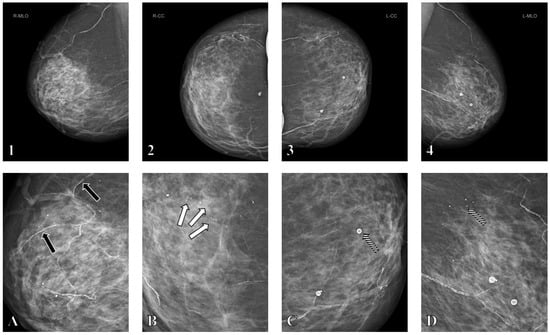

3.3. Mammographic Assessment and BAC Scoring

3.4. Multivariable Analysis